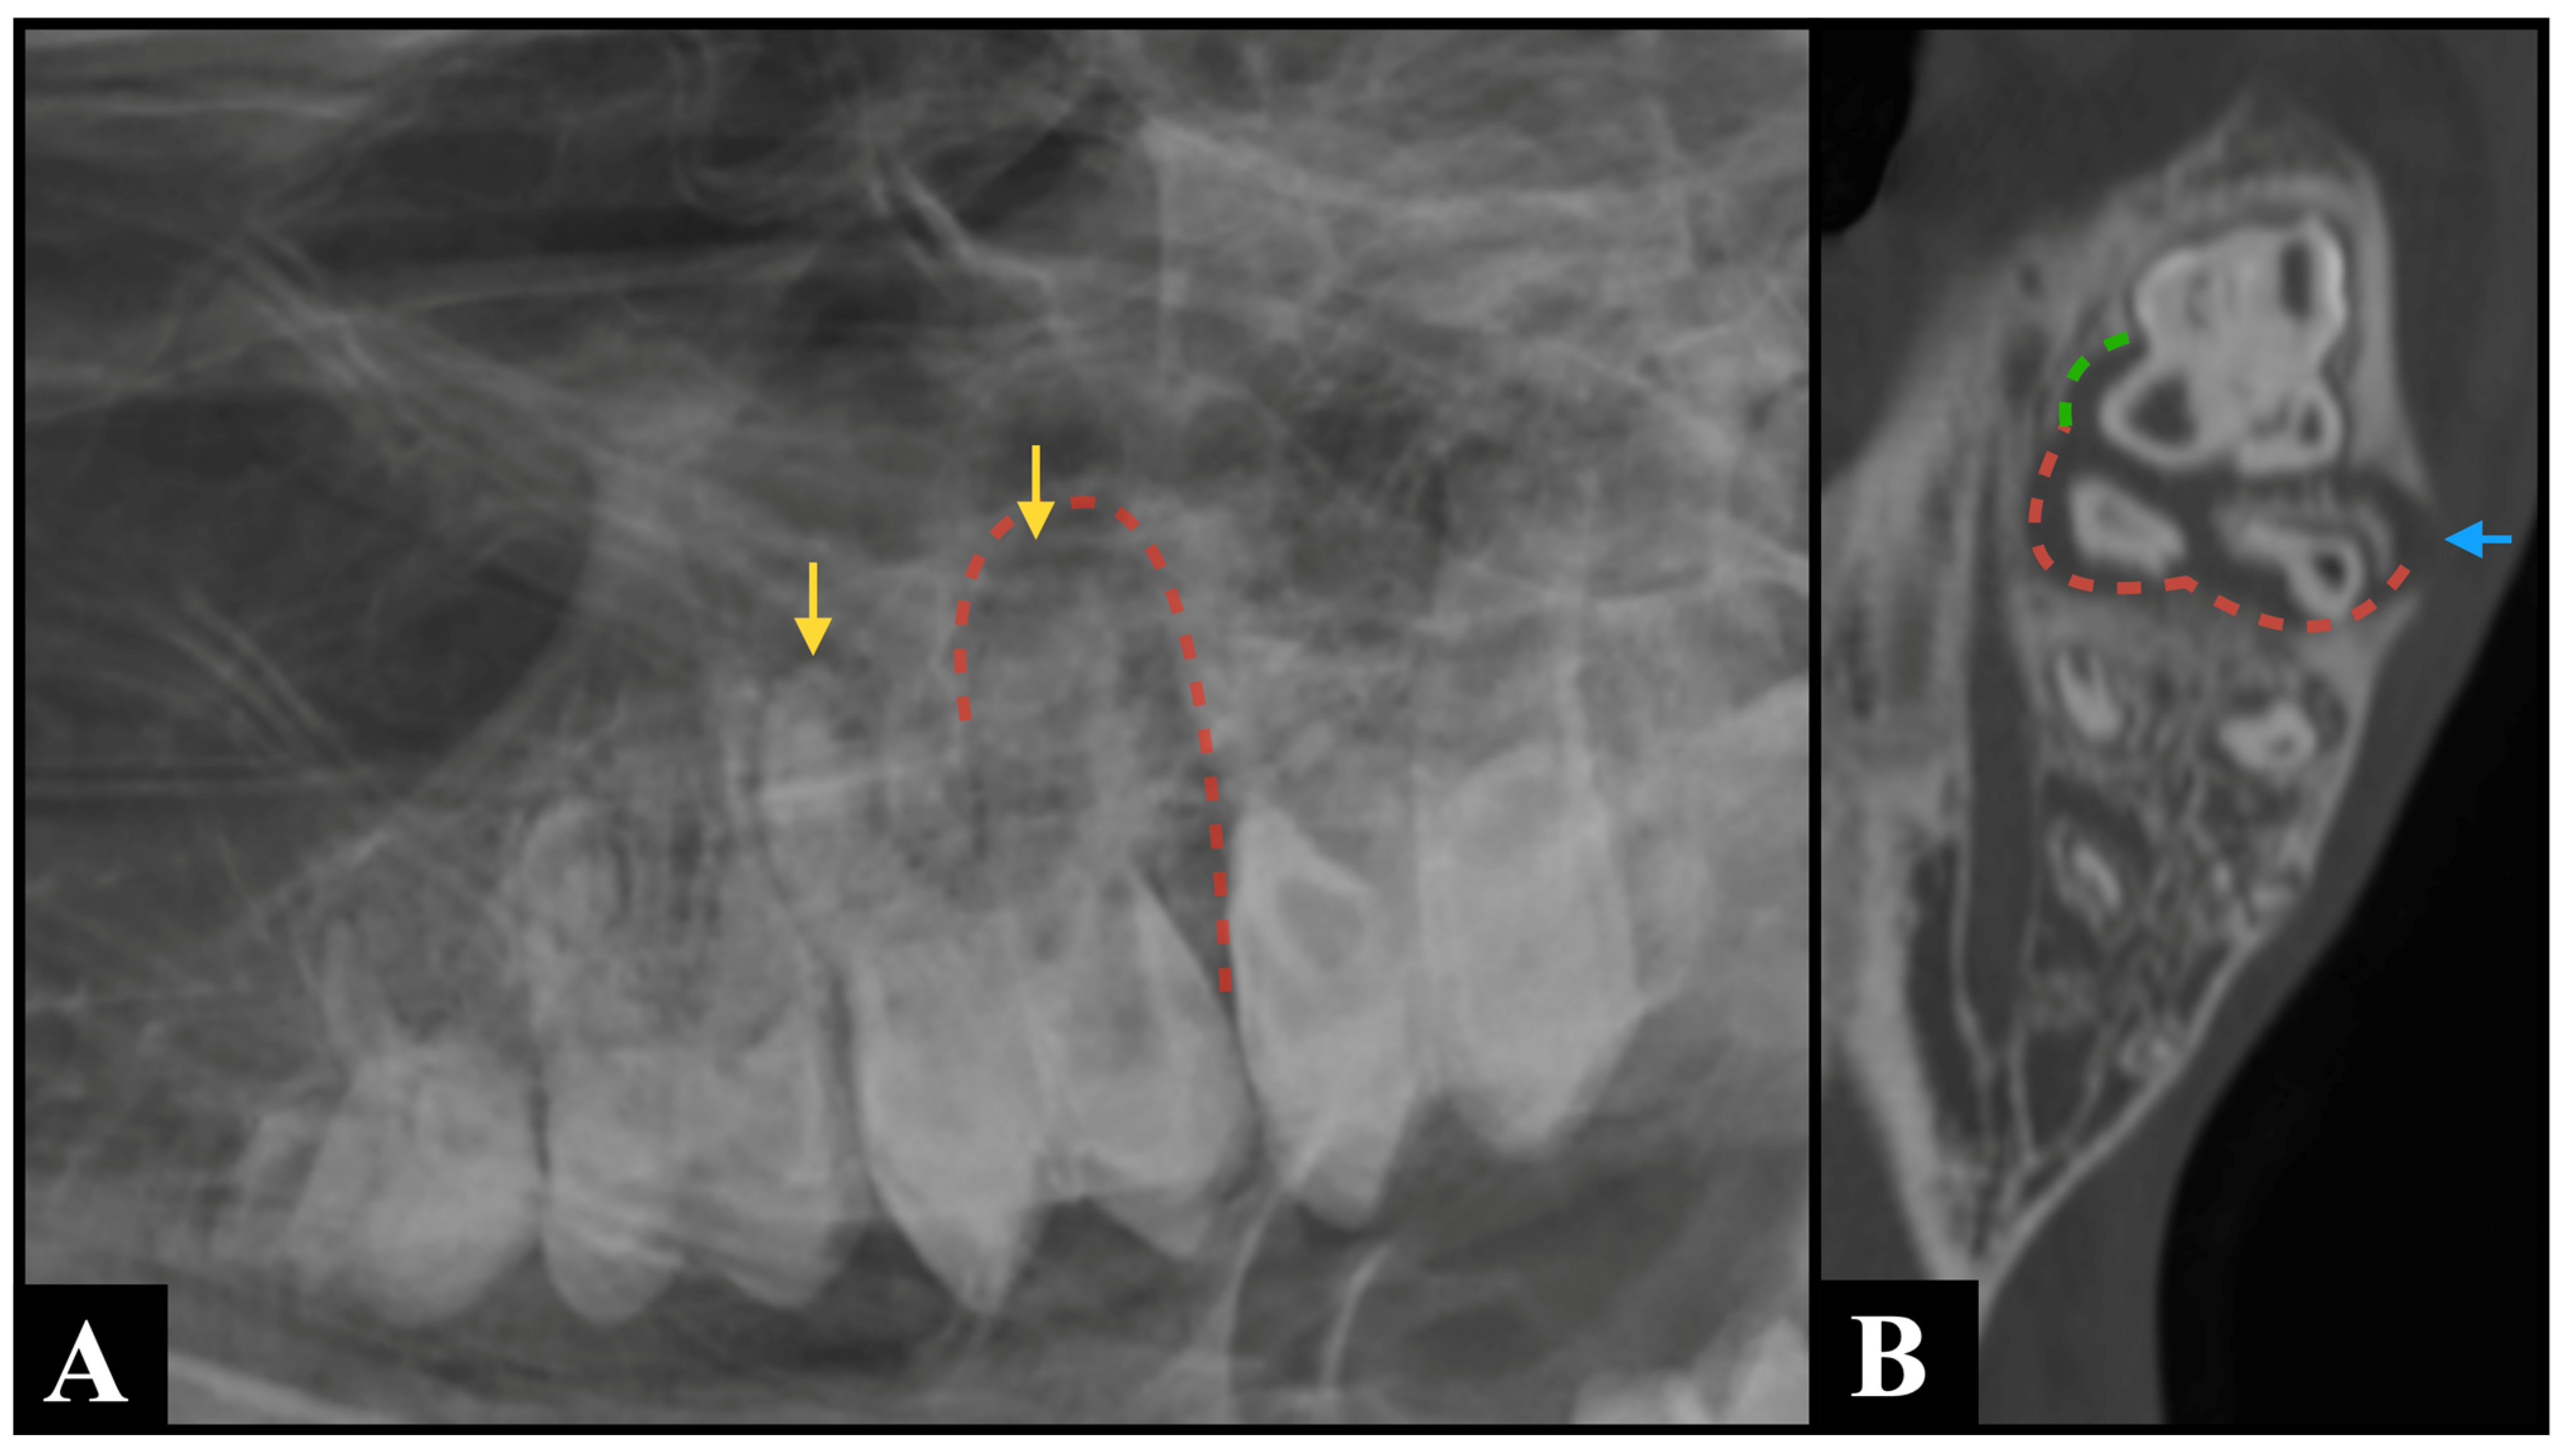

The lack of superimposition of multiple anatomical structures provided by CT is most likely the reason why widening of the periodontal ligament space, clinical crown fractures, radicular and pulpar changes, and the presence of cementomas and hypercementosis were detected more frequently by CT than by radiography in this study. Specifically, the marked over-representation of pulpar changes detected by CT compared to radiography (Figure 2) is similar to what was previously found in horses [22]. Pulpar changes included in this study were mostly represented by pulp stones, whose size makes them undetectable on radiographs. Furthermore, the possibility of performing multiplanar reconstruction is most likely responsible for the easier detection of sequestration, periosteal reaction, mandibular expansion, and cortical destruction on CT images compared to radiography. These multiplanar views allow for more precise localization and characterization of pathology, enhancing diagnostic confidence (Figure 3).

Figure 3.

An R30° D-LVO radiographic projection (A) identified shortening and blunting of the root of Triadan 210 (yellow arrows), along with widening of the periodontal ligament space (red dotted line) surrounding its distal roots, which are findings consistent with a suspected periapical infection. Bone window computed tomography multiplanar reconstructed image ((B), dorsal plane) confirmed the suspected findings (red dotted line) and provided additional information, demonstrating involvement of Triadan 211, where the mesiopalatal root exhibited widening of the periodontal ligament space (green dotted line) and an associated complete interruption of the alveolar bone (blue arrow).